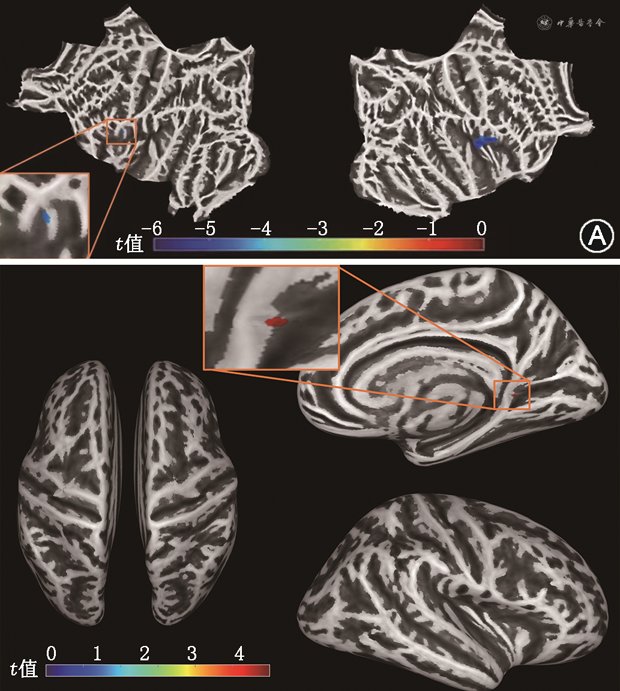

3. 基于SBM分析的组间皮质厚度和折叠系数差异:见图3及表2。与健康对照组对比,CLP组受试者的左侧额下回岛叶部、右侧脑岛部皮质厚度显著变薄(FWE校正,P=0.035)。与健康对照组对比,CLP组右侧半球扣带回峡部折叠系数增大(FWE校正,P=0.040)。

注:图例为t值,即族错误率校正后P<0.05

两组受试者SBM分析结果大脑皮质厚度和折叠系数差异有统计学意义的脑区分布

| 团块编号 | 脑区侧别 | 团块大小 | MNI坐标 | 团块水平t值 | 团块水平P值 | 解剖脑区 | ||

|---|---|---|---|---|---|---|---|---|

| x | y | z | ||||||

| 1 | 左 | 30 | -37 | 46 | 19 | -4.43a | 0.035a | 额下回:岛盖部(97%);中央前回(7%) |

| 2 | 右 | 948 | 35 | 28 | 16 | -5.19a | <0.001a | 脑岛(57%);中央前回(20%);中央后回(17%);额下回:岛盖部(6%) |

| 3 | 右 | 22 | 20 | 1 | 5 | -4.43b | 0.040b | 扣带回峡部(91%);舌回(9%) |

注:SBM为基于表面形态学的测量;MNI为蒙特利尔神经研究所;a为与健康对照(HC)组相比,伴发腭裂言语障碍的唇腭裂(CLP)组皮质厚度显著变薄(P<0.05);b为与HC组相比,CLP组折叠系数显著增大(P<0.05)